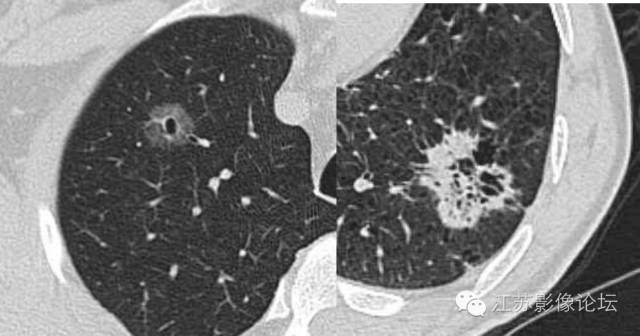

约90%毛刺结节为恶性结节,部分良性结节边缘也可见毛刺,多为长毛刺及“尖角征”。

脓腔见于炎性病灶